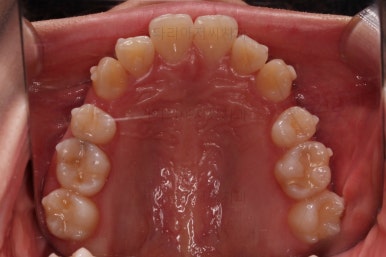

교합이 안정되었고, 치열도 가지런해졌으며 앞니 각도나 덧니 부분도 상당히 좋아졌어요.

부산교정전문의 전후 사진을 비교해 볼게요.

발치교정치고는 비교적 짧은 기간인 20개월만에 치열, 교합, 뻗친 느낌, 원하는 만큼의 입매 등 많은 점이 잘 개선된 치료였습니다.

이상 덧니, 돌출입을 가진 환자분의 인비절라인 치료사례였습니다.